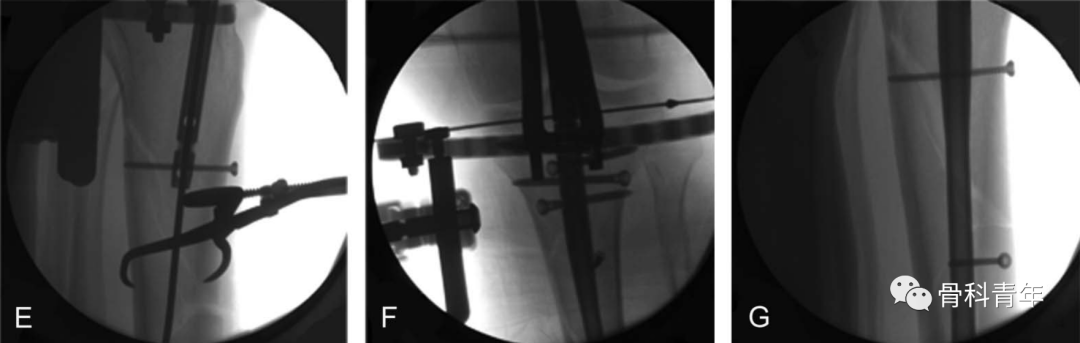

2019年JOT期刊上,国外学者改良了该方法,采用碳纤维外固定架,结合张力钢丝维持复位,取得了良好的效果。

通过在胫骨平台下方1cm,平台偏后部置入一根钢丝,另一根钢丝置入踝关节软骨下骨处,钢丝连接外侧2/3碳纤维环形架,施加110kg拉力形成张力。由于钢丝非中心置入,因此在轴向撑开时,骨折断端可能会向后成角,需要在中部后方垫消毒巾,并巾钳固定。

该外架为碳纤维,术中不影响透视,且该2/3外架,将连接杆置于小腿后方,给髓内钉的内外置钉留出空间。